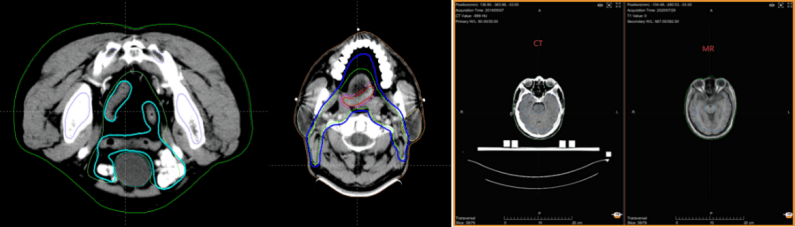

多模态图像配准和自动分割

人工智能辅助靶区勾画系统相比于传统的基于图谱(Atlas-based)的自动勾画更具有优势,成功实现了复杂靶区的自动勾画,以鼻咽癌靶区勾画为例,传统手工勾画需要2-3小时,而自动勾画只需3-5分钟,大大简化了放射治疗的流程,提高了放射治疗全流程的整体效率。